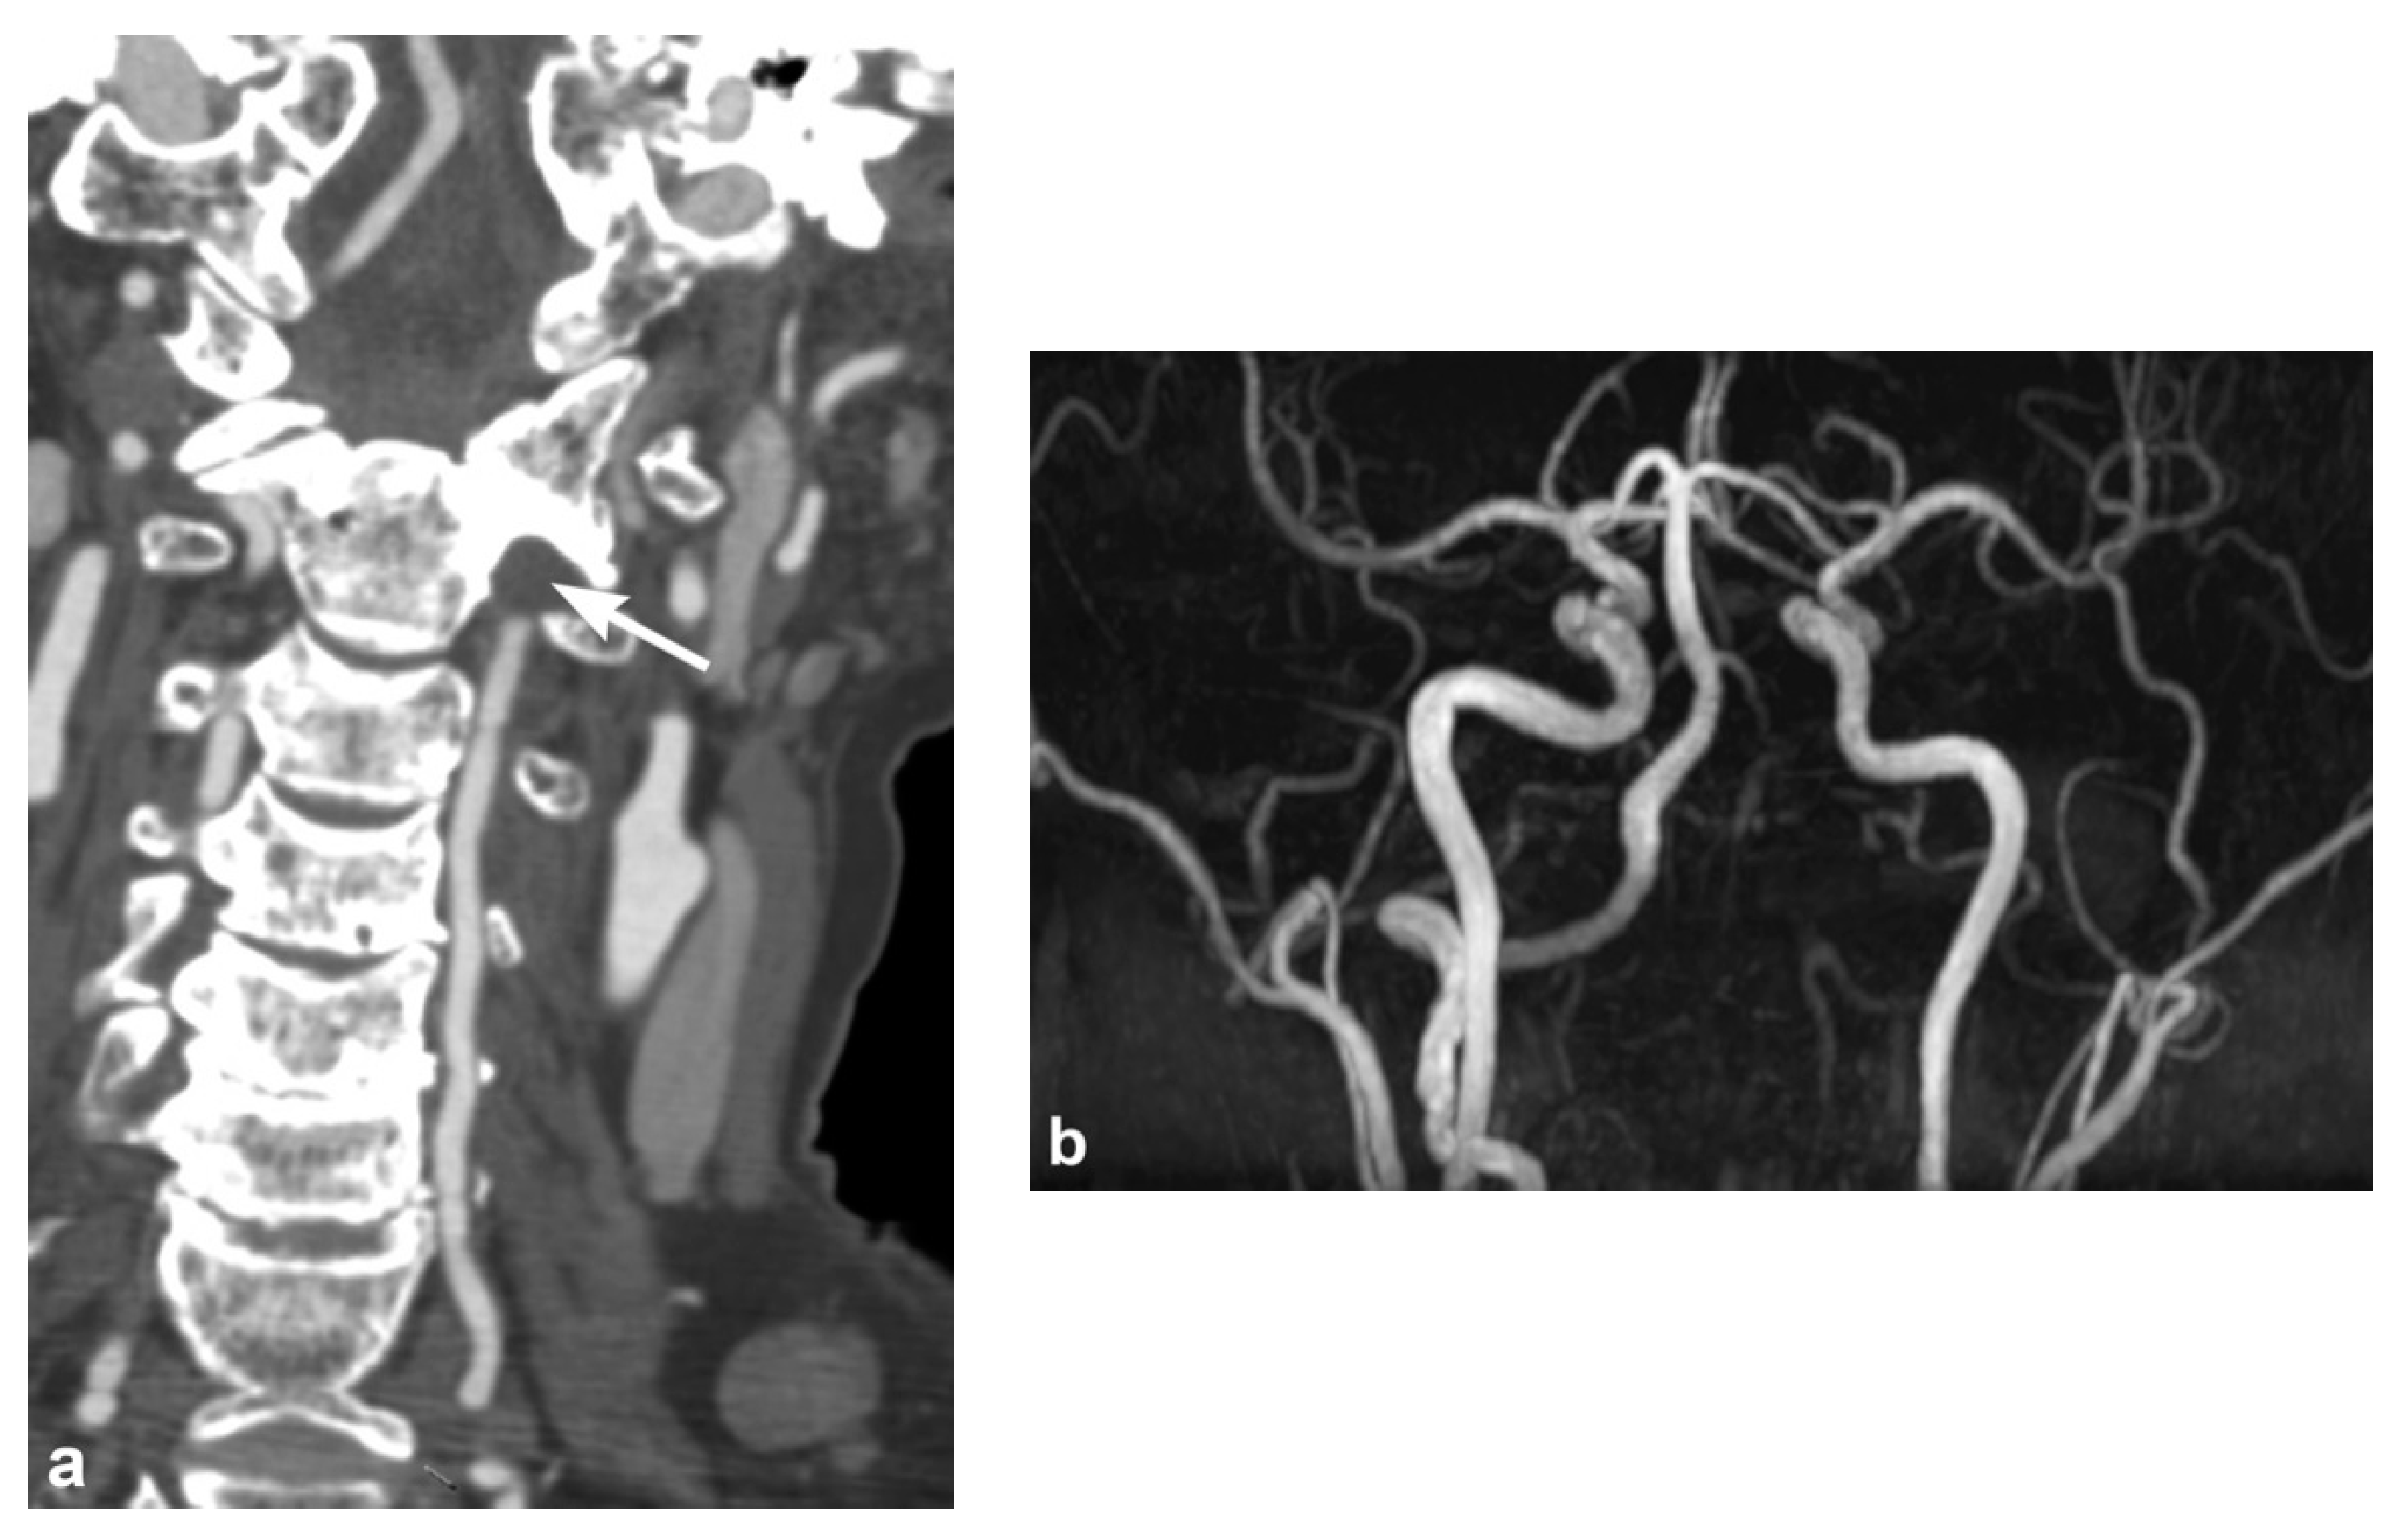

2. Imaging Techniques

3. Imaging Findings of Arterial Injury